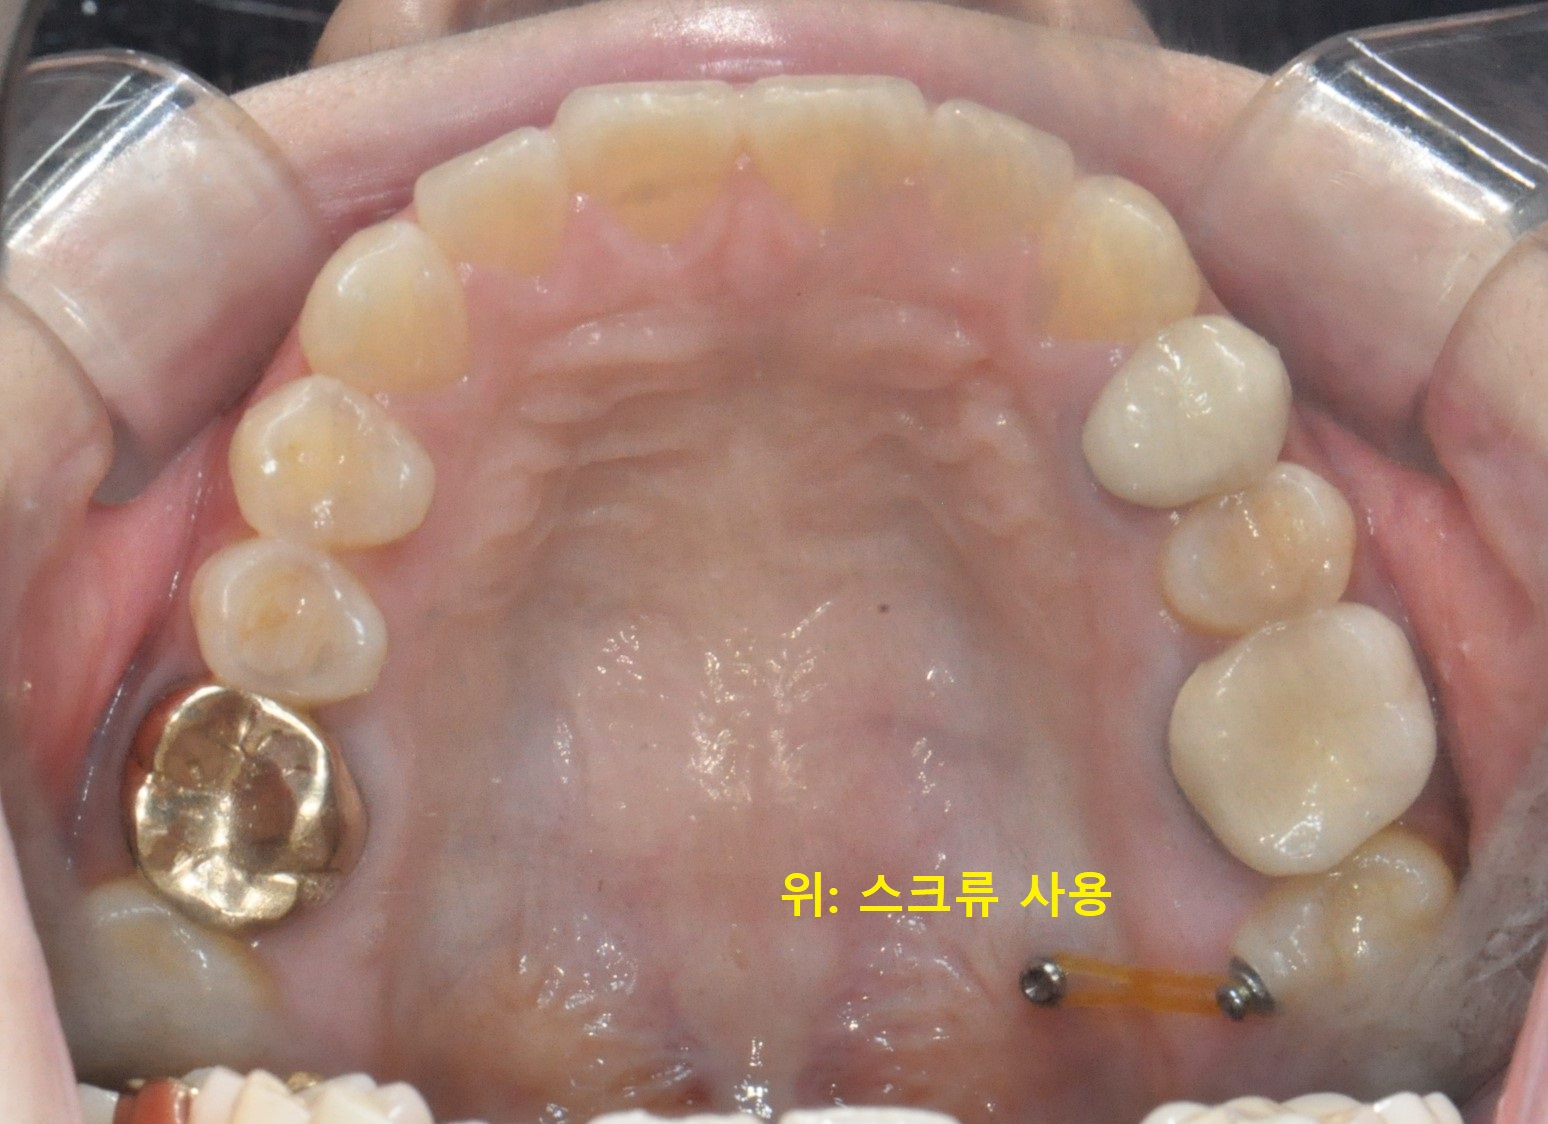

엇갈린 어금니 부분교정 (20대, 6개월)